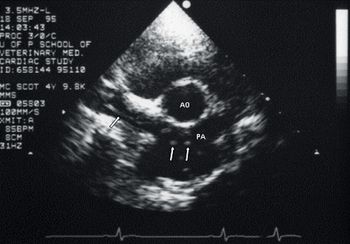

Chronic valve disease (CVD), also called mitral valve disease or endocardiosis, is the most common form of acquired cardiac disease diagnosed in small- and medium-sized dogs. The mitral valve alone is affected in 60 percent of cases of chronic valve disease, whereas only the tricuspid valve is affected in 10 percent of cases. Thirty percent will have both the tricuspid and mitral valves affected. Endocardiosis is an age-related thickening of the mitral valve due to fibroblast proliferation and an increase in collagen and elastic fibers. The thickening of the mitral valve allows a regurgitant volume of blood to be forced from the high-pressure left ventricle into the low-pressure left atrium during systole. Over time, regurgitation can lead to progressive atrial and ventricular enlargement due to volume overload. Severe mitral regurgitation can lead to left-sided congestive heart failure and pulmonary edema formation. Long-term severe mitral regurgitation can lead to generalized heart failure. Right heart..